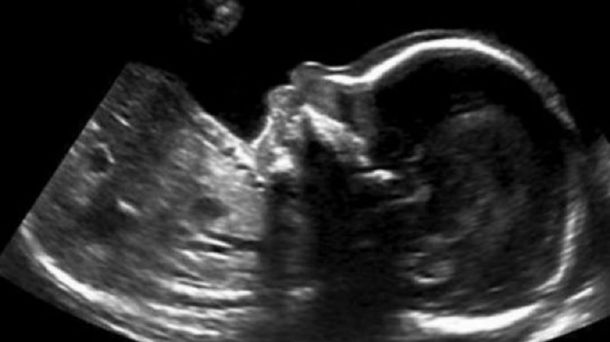

Desde el vientre materno, el pequeño en gestación se "comunicó" con sus padres. El llamativo mensaje se pudo ver a través de la ecografía. Entrá y miralo.

"Para mí era como un ´todo va a estar bien´.En Calgary, hay mucha gente sin trabajo ahora mismo y es duro para las familias. Conocemos otras dos que están en esa situación", relató Nicole quien además contó que ese mismo día sabían que quien estaba creciendo en su vientre,era un varón.